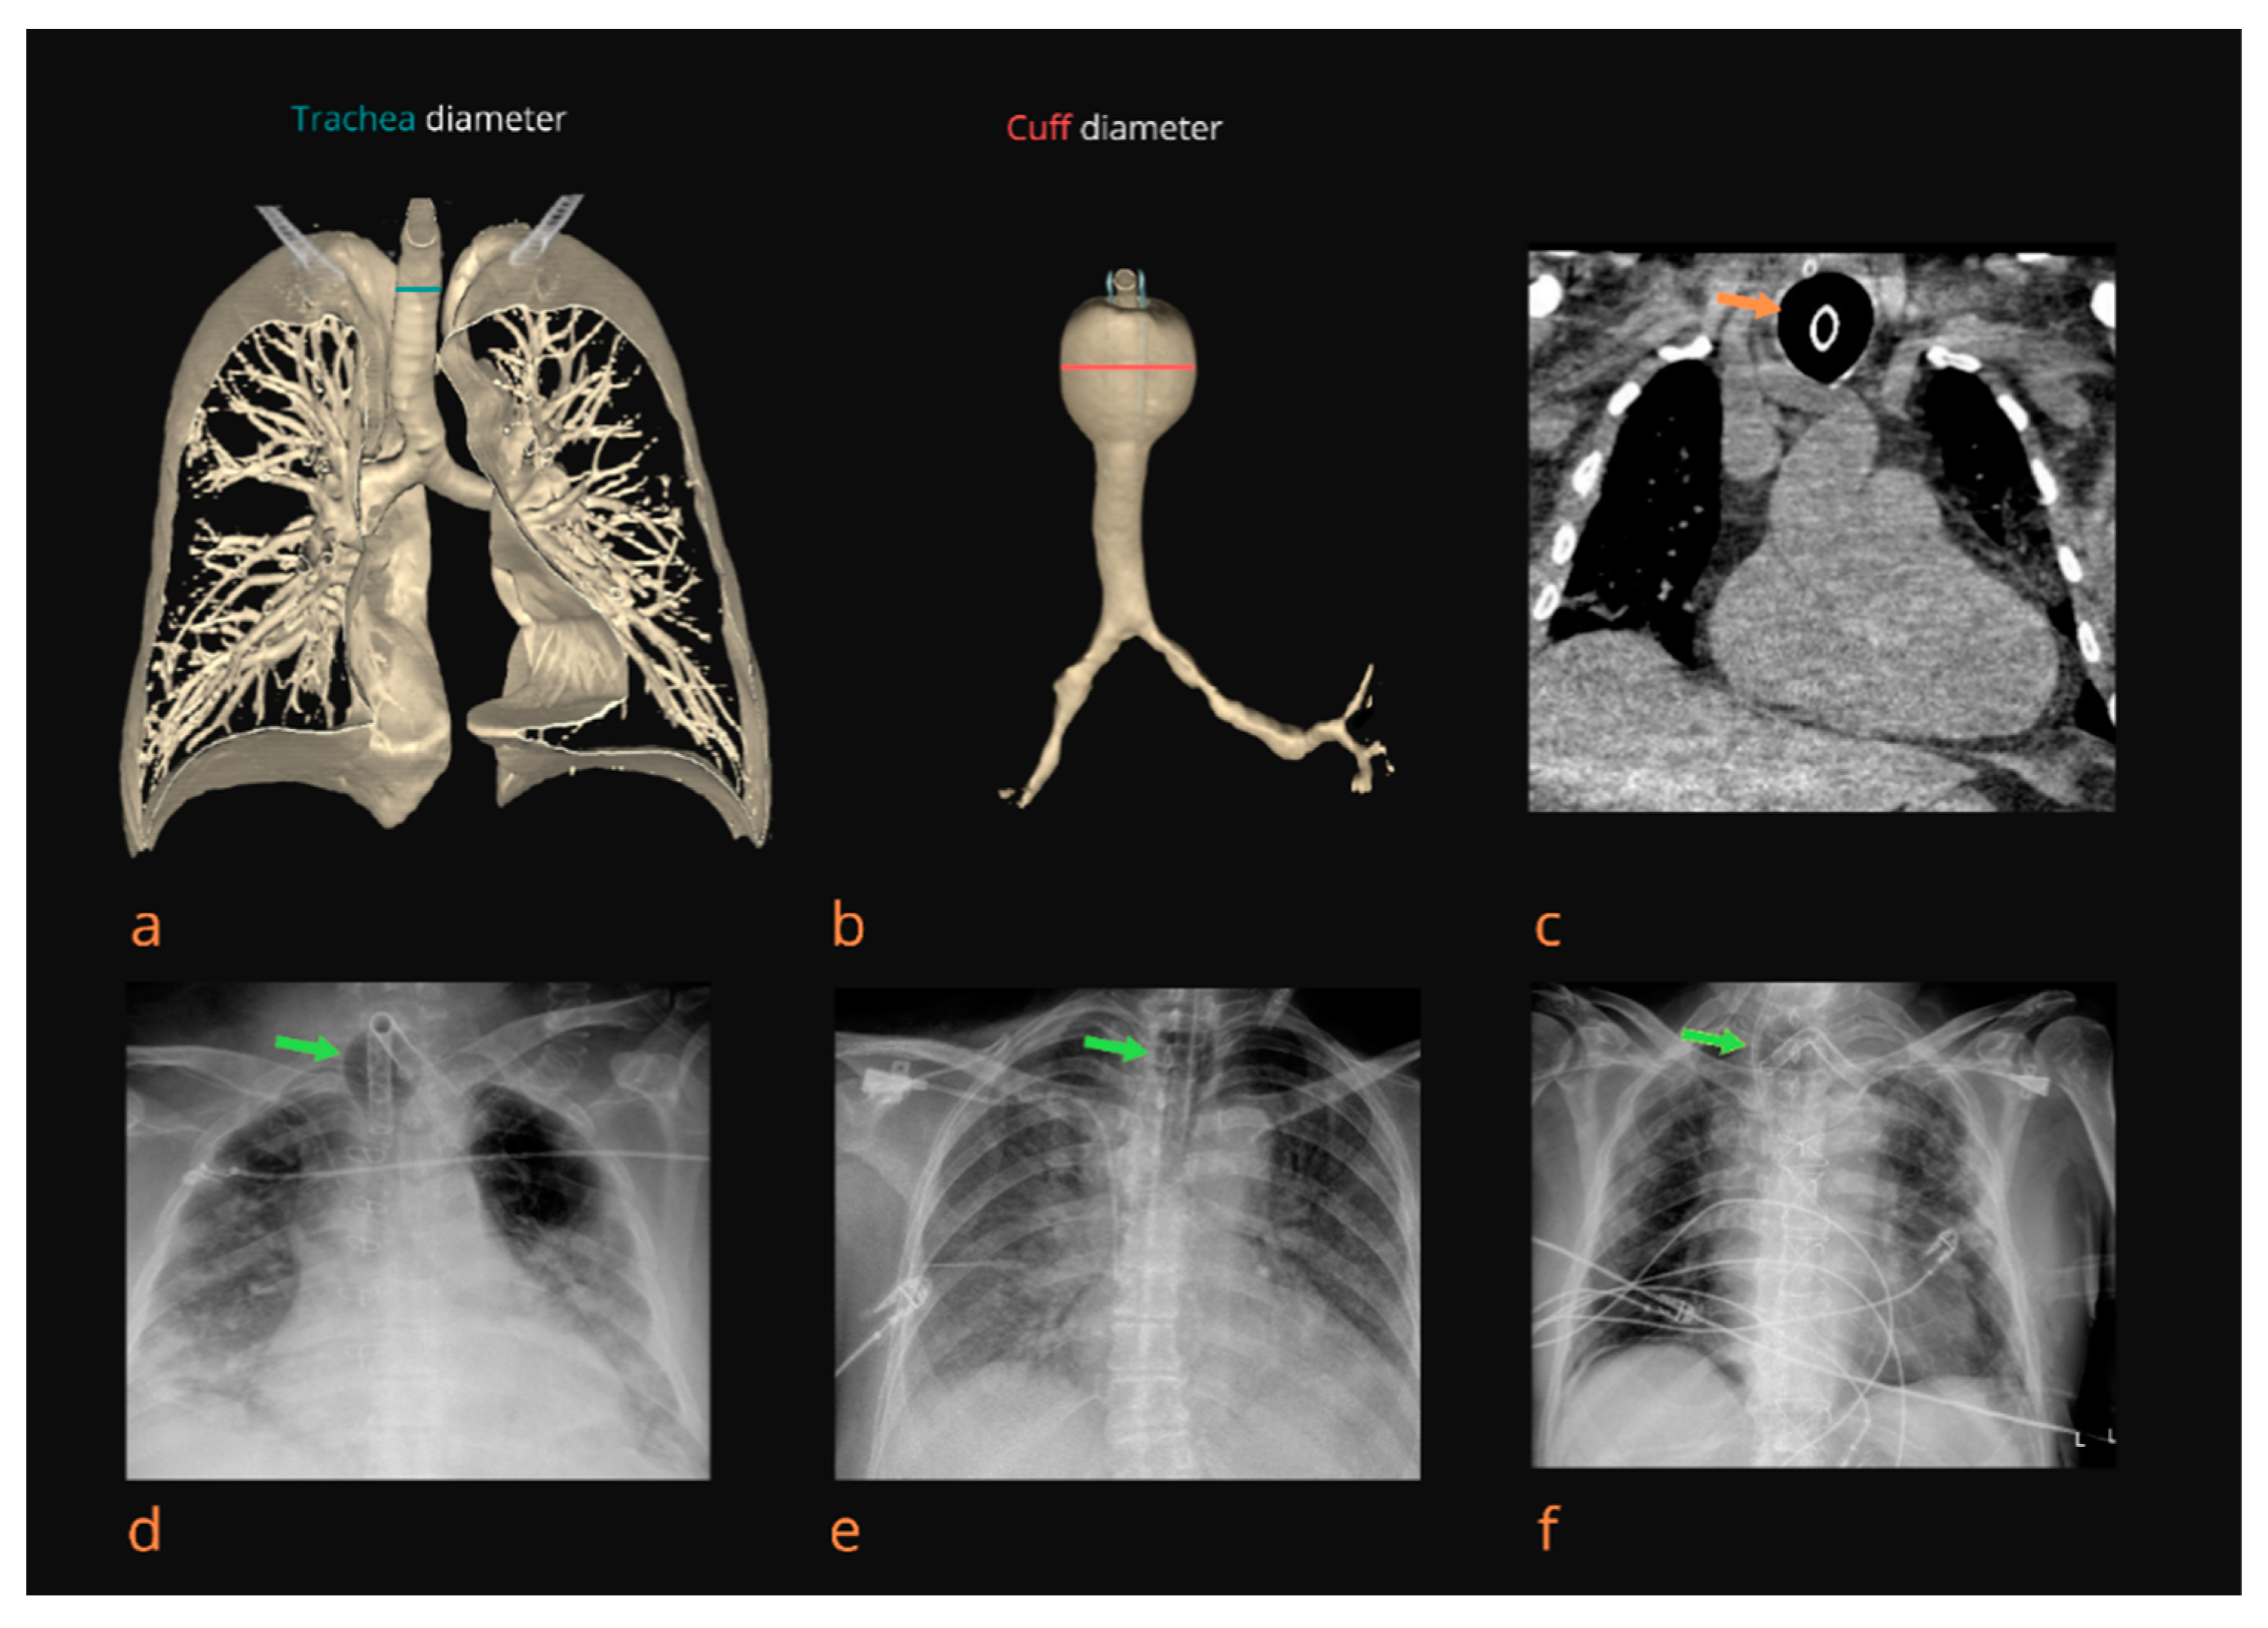

All patients were treated according to COVID-19 treatment protocols, which included an initial chest X-ray at admission. In all included patients, the trachea lumen diameter was measured at the level of the clavicle on the initial chest X-ray image in the coronal plane; in the group of patients treated with MV, the trachea lumen diameter was measured before endotracheal intubation and was measured continuously in millimeters (Figure 1 and Figure 2). All the results were measured twice by two independent investigators. After the intubation, the trachea lumen diameter was measured at the level of the inflated cuff around the endotracheal tube. Additionally, we calculated the cuff/trachea (C/T) diameter ratio using the following formula: the trachea diameter at the cuff area at the last measurement/initial trachea diameter before intubation [6].

Figure 1.

Radiological diagnosis of tracheomegaly (TM). A 3D view (CT scan) of the tracheobronchial tree with determination of the diameter of the trachea (T diameter) in the clavicular area (a). A 3D view (CT scan) of the trachea with TM and determination of the diameter of the trachea in the cuff area (C diameter) (b). Native CT scan of the thorax thirteen days after intubation. A coronal plane showing TM in the cuff area (orange arrow) with a C/T diameter ratio of 2.31 (c). Chest X-ray shows TM (green arrow) in the area of the tracheostomy tube cuff nine days after intubation with a C/T diameter ratio of 2.12 (d). Chest X-ray shows TM (green arrow) in the cuff area of the endotracheal tube 8 days after intubation with a C/T diameter ratio of 1.95 (e). TM (green arrow) visible on a chest X-ray twelve days after intubation and three days after a tracheotomy with a C/T diameter ratio of 2.02 (f).